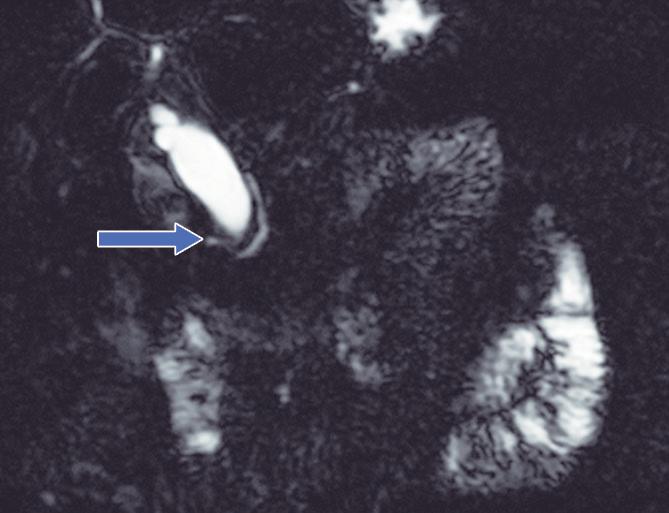

Conducto biliopancreático común largo

La unión entre el conducto colédoco y el conducto pancreático ocurre de diversas maneras, la mayoría son consideradas variantes normales y no tienen implicancias clínicas. Suelen confluir en un canal común con una longitud menor a los 5 mm y con un ángulo variable, alternativamente puede existir un ingreso al duodeno de ambos conductos por separado. En el canal común biliopancreático largo existe una unión precoz del colédoco con el conducto pancreático, con confluencia proximal al esfínter de Oddi por fuera de la pared duodenal. Para su diagnóstico se requiere una distancia mayor o igual a 15 mm entre la papila mayor y la confluencia de ambos conductos (Figura 6). Este conducto común largo permite el reflujo de las secreciones pancreáticas al colédoco, aumentando la presión intraductal y favoreciendo el desarrollo de quistes coledocianos. También favorece el reflujo de bilis hacia el conducto pancreático y, como consecuencia, predispone a la PA y PAR. 14,15

Figura 7. Conducto biliopancreático común largo

La flecha blanca señala la unión precoz del conducto colédoco con el conducto pancreático principal, alejada de la pared duodenal - papila mayor (cabeza de flecha), conformando un conducto biliopancreático común largo (> 15 mm).

A) Colangio-RM. La flecha señala la unión precoz del conducto colédoco con el conducto de Wirsung, alejado de la pared duodenal, conformando un conducto biliopancreático común largo. Se observa, como complicación, el desarrollo de un quiste de colédoco (cabezas de flecha). B) Colangio-RM magnificada. Medición de la distancia entre la pared duodenal, en el sitio de la papila mayor y la unión de los conductos colédoco y pancreático. C) Resonancia magnética, secuencia T1 con gadolinio, plano coronal. Unión de los conductos (flecha). Pared duodenal - papila mayor (cabeza de flecha).